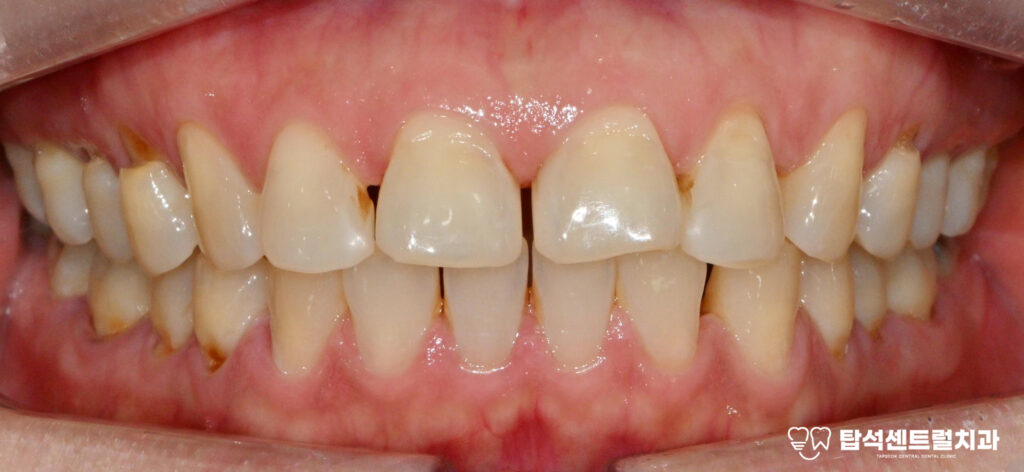

특히 심한 치아 통증을

동반하는 경우 치주염 증상이

유력해집니다.

우선 잇몸이 붉어지면서 가벼운

자극에도 쉽게 출혈이 발생하게 됩니다.

또한 차갑거나 뜨거운 음식,

단 음식을 먹을 때 치통이

계속 발생할 수 있습니다.

그리고 고름이 나오거나

염증이 발생하여 통증이

생기는 경우가 있습니다.